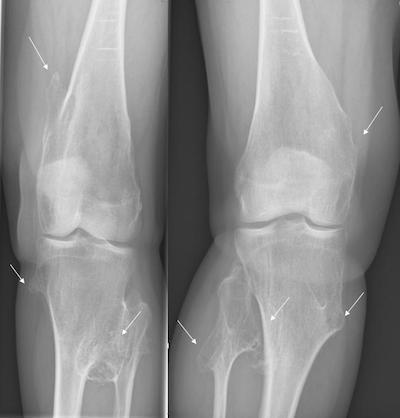

骨软骨瘤病与内生软骨瘤病简介临床上,在所有的良性软骨系统肿瘤中,以骨软骨瘤和内生软骨瘤最为常见。骨软骨瘤和内生软骨瘤多为单发,一旦发病部位达到两处及以上,即可相应诊断为骨软骨瘤病和内生软骨瘤病。这是两种罕见但重要的骨骼疾病,对病人的生活质量和健康状态有着显著的影响,往往在儿童及青少年时期由于骨骼畸形及生长障碍就医而被诊断。成年后,由于关节对位不良,常常导致关节疼痛和退行性变。更为重要的是,尽管两者为良性病变,但均具有恶变为软骨肉瘤的风险。因此,本文将重点介绍这两类疾病的病因、症状、主要治疗方法,以及预防疾病恶变需要注意些什么,供大家学习交流。一、骨软骨瘤病骨软骨瘤病(多发骨软骨瘤),又被称为遗传性多发性外生骨疣(MultipleHereditaryExostoses,MHE),是一种常染色体显性遗传病。它主要表现为多个外生骨疣(即骨软骨瘤)在骨骼表面背向关节生长,这些外生骨疣可以在全身各处出现,但尤其常见于长骨的干骺端,如股骨、胫骨和肱骨,也常见于中轴骨,如骨盆、肩胛骨和脊柱。1.遗传特点骨软骨瘤病的发生与EXT1或EXT2基因的突变有关,约70-94%的多发骨软骨瘤病患者存在EXT1/2胚系突变。EXT1基因在染色体8q24区域,EXT2基因位点在11p11-13,骨软骨瘤病以EXT1突变更为常见。EXT基因编码的蛋白质Exostosin参与了细胞表面的分子信号传导,包括对多种生长因子的组织分布及生物有效性的调节。当EXT1或EXT2基因突变时,会影响软骨细胞的信号传导,导致软骨细胞过度增殖和骨骼发育异常。骨软骨瘤病作为显性遗传病,意味着只要父母中有一方携带这种突变基因,子女就有同等几率患病。两个显著的特点为,(一)、男性患者由于青春期长,生长板闭合较晚,因此一般男性畸形程度较女性重。(二)、EXT1基因突变的患者表型特征更突出,无论男女,身体骨软骨瘤的数量、肢体的短缩程度、身材矮小程度和中轴骨受累的几率都比EXT2基因突变更为明显(p<0.0005)(JBoneJointSurgAm,2011;ClinOrthopRelatedRes,2015)。2.临床表现骨软骨瘤病通常在儿童时期发病,随着骨骼的生长,外生骨疣的数量和大小会逐渐增加。患者主要症状包括:1)骨骼畸形和身材矮小:骨软骨瘤会导致骨骼生长异常和畸形,从而影响身高。2)疼痛和功能障碍:骨软骨瘤可能会压迫周围的肌肉、肌腱、神经和血管,导致疼痛和功能障碍。3)关节活动受限:骨软骨瘤会影响关节活动,导致关节活动受限。4)恶变风险:虽然骨软骨瘤病是良性疾病,但仍有恶变为软骨肉瘤的风险,这种恶变通常发生在成年患者身上,恶变率为5%左右。意大利Rizzoli研究中心研究了多发性骨软骨瘤的基因型-表型的相关性,调查了529名患者,将患者分为轻、中和重三型(如下表),26例恶变患者多发骨软骨瘤的诊断年龄平均为7.6岁,恶变诊断年龄平均为28.6岁。恶变为软骨肉瘤的部位最多见于骨盆和肩胛骨,但未发现恶变的风险与性别、畸形程度、骨软骨瘤的数量以及EXT1/2突变显著相关(JBoneJointSurgAm,2011)。3、临床分型临床上按照患者表型特征分为轻(I型),中(II型)和重(III型)三型。529患者中1/4为重型,其他3/4为轻中型(轻/中型约1:1)。(来自JBoneJointSurgAm,2011)典型病例男性,29岁,自幼诊断为多发骨软骨瘤,因骨盆部位包块入院,术前检查怀疑骨盆骨软骨瘤恶变,手术行肿瘤切除,保留髋关节后柱,股骨头髋臼重建,假体置换,术后病理确诊软骨肉瘤I级,现为术后10年,肿瘤未复发,功能良好。随访10年行走视频二、内生软骨瘤病内生软骨瘤病(多发内生软骨瘤,Enchondromatosis)是一种非遗传性基因突变导致的疾病,主要特征为骨内多处出现内生软骨瘤。这些软骨瘤通常是良性的,但在某些情况下可以恶变为软骨肉瘤。Ollier病和Maffucci综合征是内生软骨瘤病最常见的两种类型。Ollier病:以多发性内生软骨瘤为特征,通常累及长骨和扁平骨,如股骨、胫骨、骨盆等。患者可能在儿童时期就表现出症状,随着骨骼成熟,软骨瘤的数量和大小可能会增加。Ollier病患者除了骨骼畸形外,还可能面临骨折和疼痛的风险。Maffucci综合征:即软骨营养障碍-血管瘤综合征,是一种更为罕见的内生软骨瘤病,其特点是多发性内生软骨瘤与多发性软组织血管瘤同时存在。血管瘤通常位于上肢,如手部和前臂,但也可能出现在下肢和躯干。Maffucci综合征患者除了骨骼畸形外,还可能面临血管瘤破裂出血和内生软骨瘤恶变为软骨肉瘤的风险。女性,63岁,Maffucci综合征,骨盆及股骨近远端受累,股骨畸形。左侧骨盆内生软骨瘤恶变为软骨肉瘤。1.遗传特点内生软骨瘤病的病因尚未完全明确,但研究表明,非遗传性基因突变起着重要作用。IDH1基因位于染色体2q33.3,IDH2基因在15q26.1,IDH基因编码一种酶称为异柠檬酸脱氢酶,这种酶在细胞内催化异柠檬酸转化为α-酮戊二酸。IDH1/2突变见于81%Ollier病和77%Maffucci综合征患者。IDH1突变常见的类型是在IDH1基因的第132位氨基酸发生突变,替换了精氨酸(arginine,R)为组氨酸(histidine,H),因此被称为R132H突变。IDH2基因突变发生在第四外显子的R140和R172。IDH1/2突变导致酶活性的异常改变,使其催化产物从α-酮戊二酸转变为2-羟戊二酸(2-hydroxyglutarate,2-HG),细胞内促癌代谢产物2-HG异常积累,影响骨骼发育,导致内生软骨瘤的形成。需要强调的是,内生软骨瘤病并非遗传性疾病,因此患者的家族成员通常不会患病。2.临床表现内生软骨瘤病早期通常不伴明显症状,随着骨骼的生长,内生软骨瘤的数量和大小也会逐渐增加。患者可能出现骨骼畸形、关节活动受限等症状。在严重病例中,软骨瘤可能累及整个骨骼系统,导致严重的残疾。此外,与骨软骨瘤病类似,内生软骨瘤病也存在恶变为软骨肉瘤的风险。恶变率因病情严重程度而异,但总体上高于骨软骨瘤病,其中在Maffucci综合征患者中,恶变率甚至高达50%以上。因此,内生软骨瘤病患者同样需要定期复查。三、治疗方法与管理策略目前,对于骨软骨瘤病和内生软骨瘤病尚无有效的药物治疗方法。对于无症状或症状轻微的患者,通常无需治疗,只需定期随访观察。然而,当骨疣或内生软骨瘤压迫周围组织、引起疼痛或关节活动受限时,手术治疗是可供选择的手段,手术方法包括切除骨疣、矫正畸形等。对于成年患者和恶变风险较高的患者,定期复查尤为重要。通过X线、CT和MRI等影像学检查手段,可以及时发现并处理恶变病灶。四、骨软骨瘤病和内生软骨瘤病的异同五、总结与展望因此回到本文的标题上,骨软骨瘤病是遗传性疾病,而内生软骨瘤病是非遗传性疾病。二者均是罕见的骨骼疾病,虽然它们是良性的,但仍有恶变为软骨肉瘤的风险。定期随访和及时治疗可以帮助预防恶性变,改善患者的预后。

骨软骨瘤:一种常见的良性骨病变骨软骨瘤,是青少年时期骨骼发育过程中形成的一种良性肿瘤,在人群中并不少见。通常是孤立生长的肿物,不伴有疼痛(图1)。在部分病例中,可见多发性骨软骨瘤(图2),这可能与某些基因突变相关,具有家族遗传特征。(一)骨软骨瘤会变成恶性肿瘤吗?存在恶变的风险,但是风险极低。恶变风险:孤立生长骨软骨瘤(<1%)小于多发性骨软骨瘤(1%-5%)。绝大部分的骨软骨瘤随着青春发育期结束保持稳定,不再生长。骨软骨瘤需要定期拍片子评估是否生长,监测骨软骨瘤的大小和形态是否发生改变。(二)骨软骨瘤的临床表现大部分没有特殊不适,通常是检查意外发现无痛骨性包块肿物表面的滑囊发炎或者刺激周围的韧带,可以出现疼痛压迫症状:神经受压,出现疼痛、麻木;血管受压,出现肢体缺血表现严重病例中,多发性骨软骨瘤可导致儿童骨骼畸形(三)骨软骨瘤的治疗对于绝大部分孤立性骨软骨瘤,没有症状,不需要特殊治疗;但是需要定期复查X线,观察大小和形态改变如果引起疼痛、压迫症状等,或者复查X线发现肿物大小、形态有改变(发生恶变的征兆),可以选择手术切除,术后存在一定复发风险对于多发性骨软骨瘤,建议手术切除